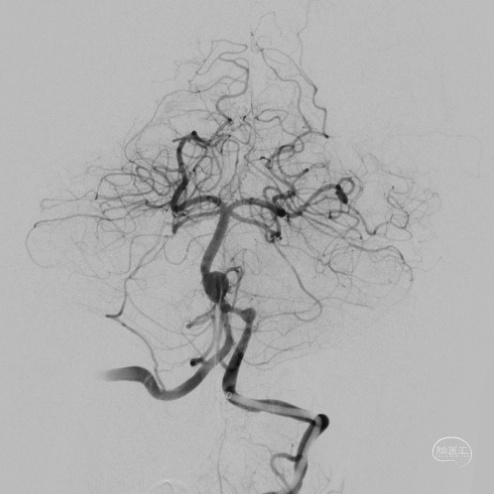

DSA:

3D重建显示基底动脉下部、双椎结合部、左椎多发夹层动脉瘤: